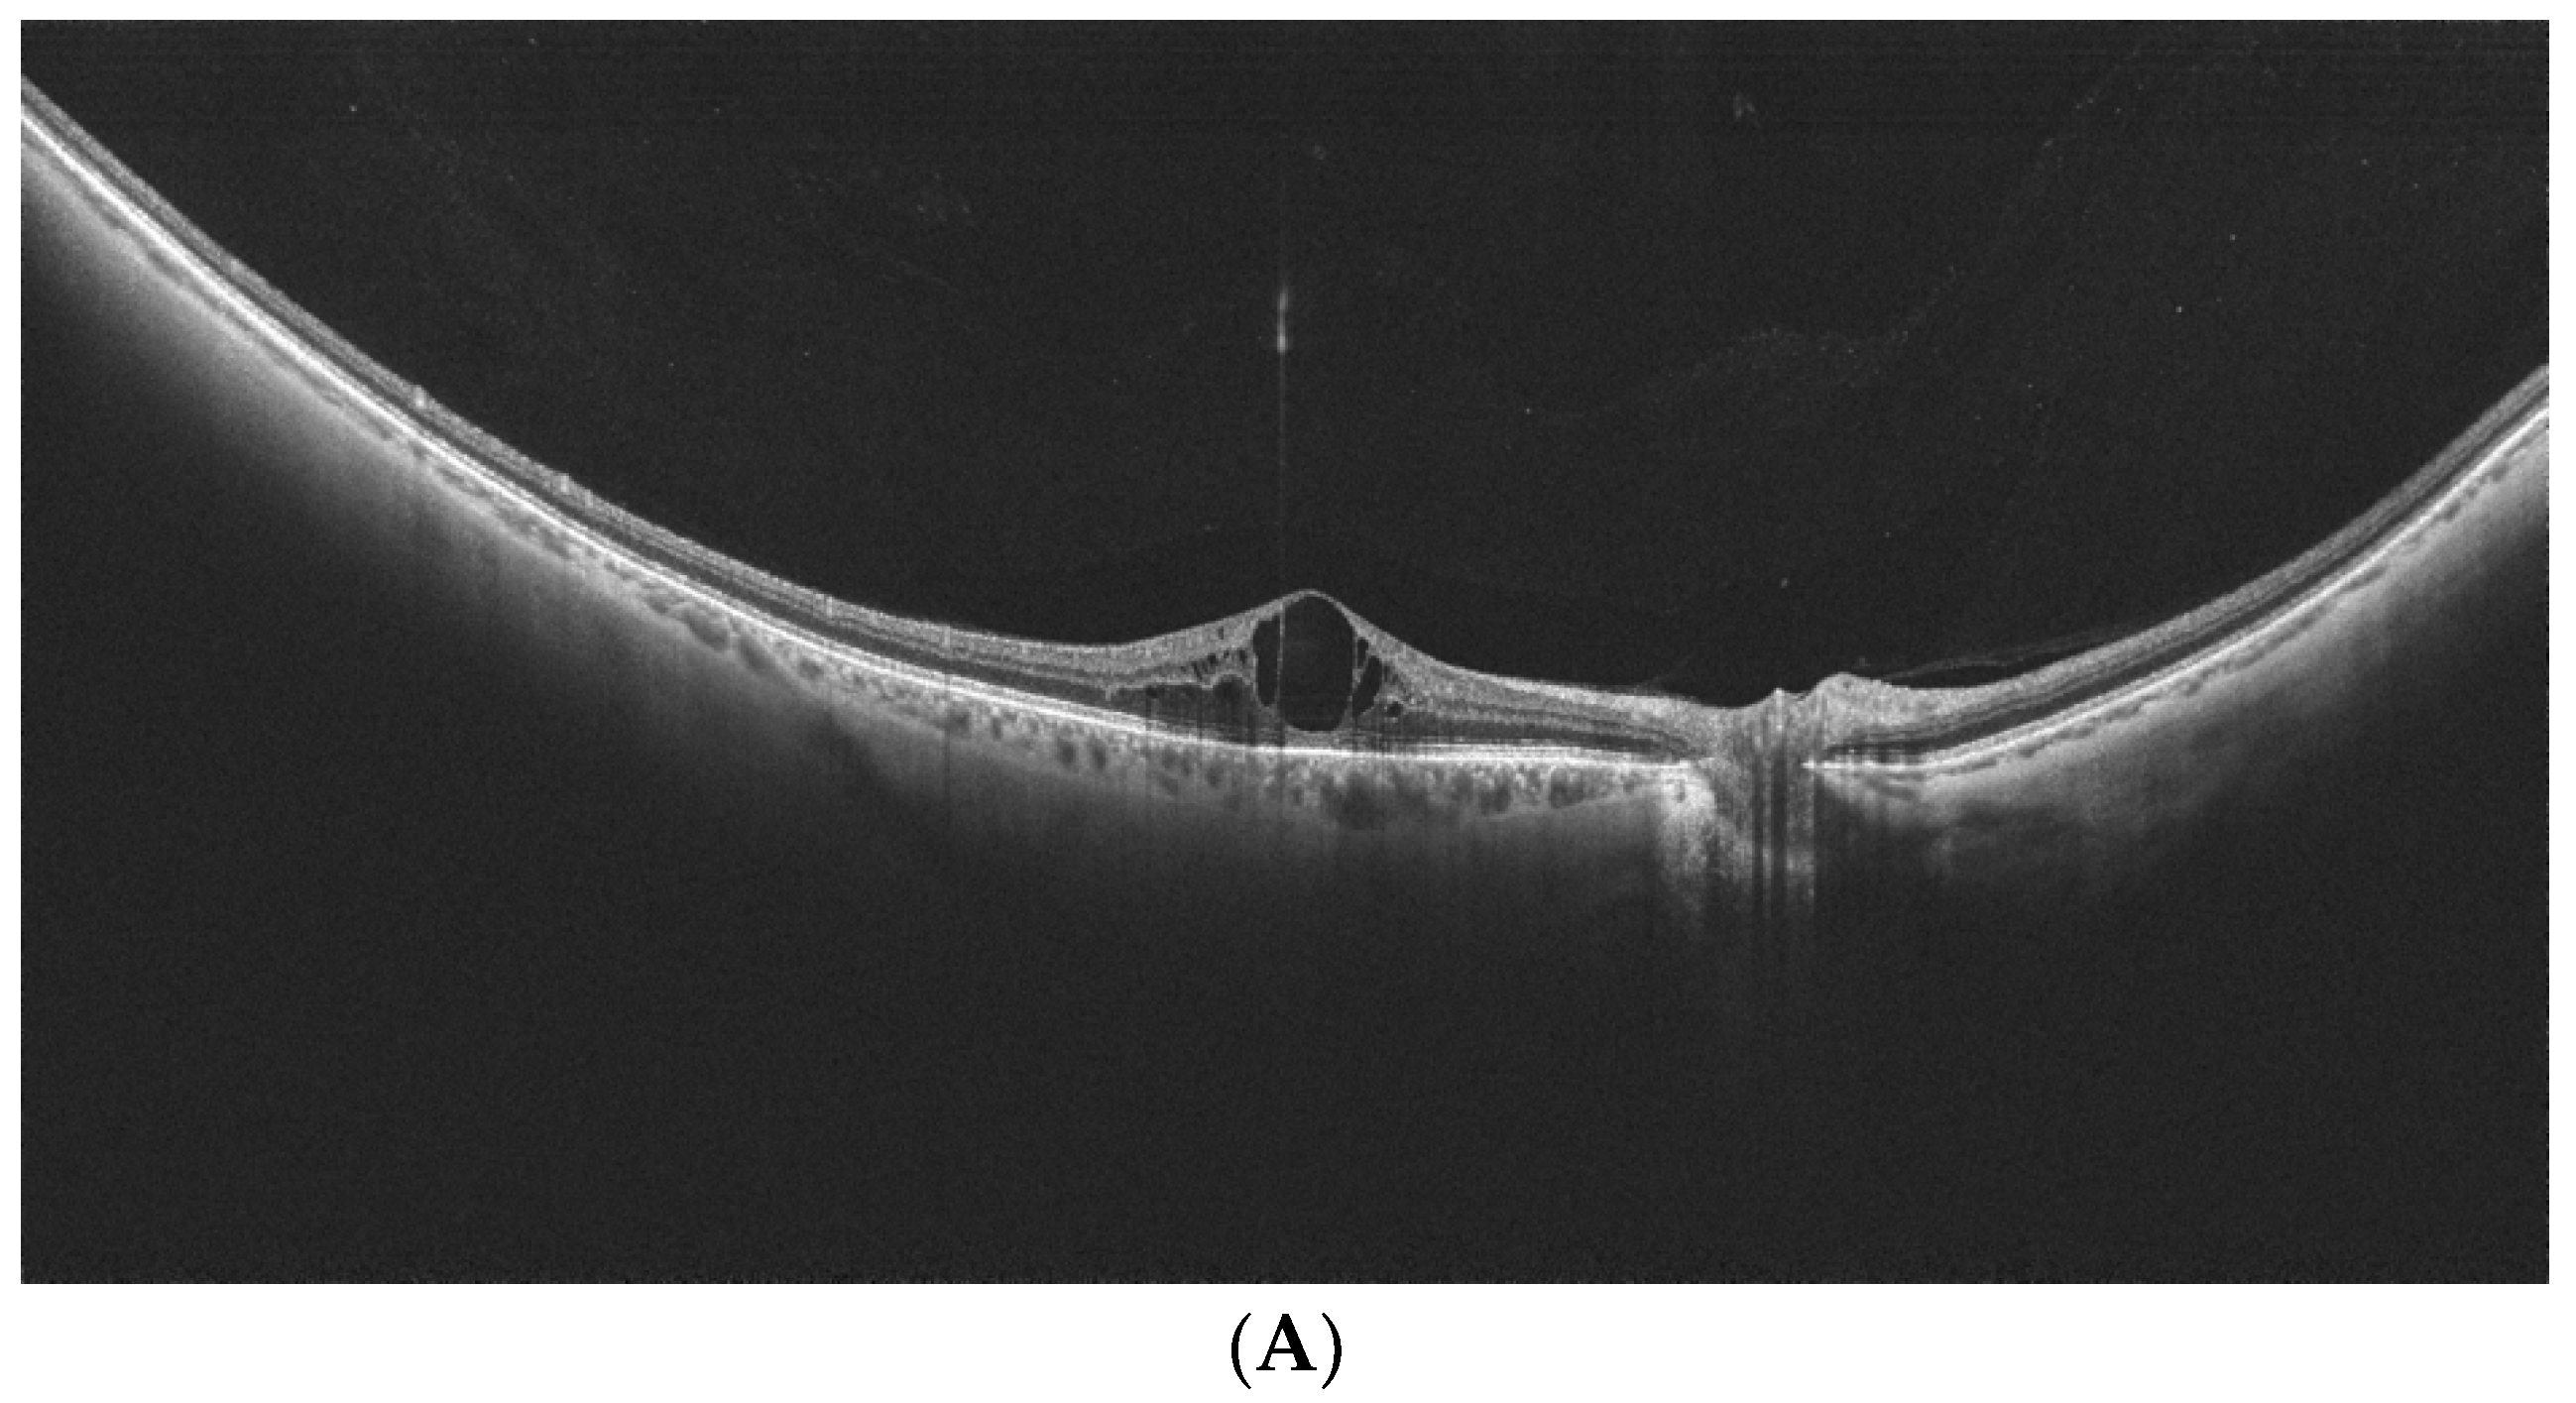

- Govetto, A.; Sebag, J.; Lucchini, S.; Ballabio, C.; Matteucci, M.; Ranno, S.; Carini, E.; Virgili, G.; Bacherini, D.; Radice, P. Imaging rhegmatogenous retinal lesions and peripheral vitreo-retinal interface with wide-field optical coherence tomography. Retina 2023, 44, 269–279. [Google Scholar] [CrossRef] [PubMed]